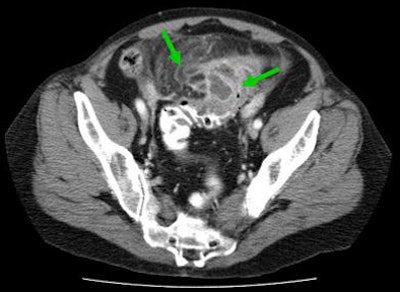

![]() |

| Locally complicated cases with hemorrhage and perforation often reveal a "lucky hat" sign, indicating active migration of omental fat that drives local inflammation. Extracolonic abscess formation indicates stage IIB disease by the Hanson/Stock staging method and stage II by the modified Hinchey system. |